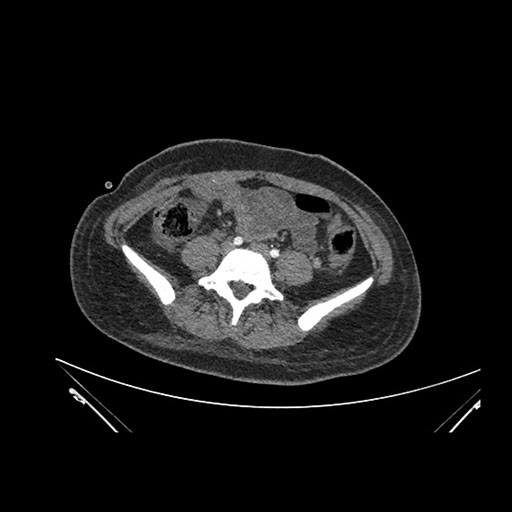

Imaging Analysis

Look through the patient's CT scan to identify any areas of concern for the necessary procedure.

Axial Arterial

Based on initial findings, which issue(s) would you be most concerned about?